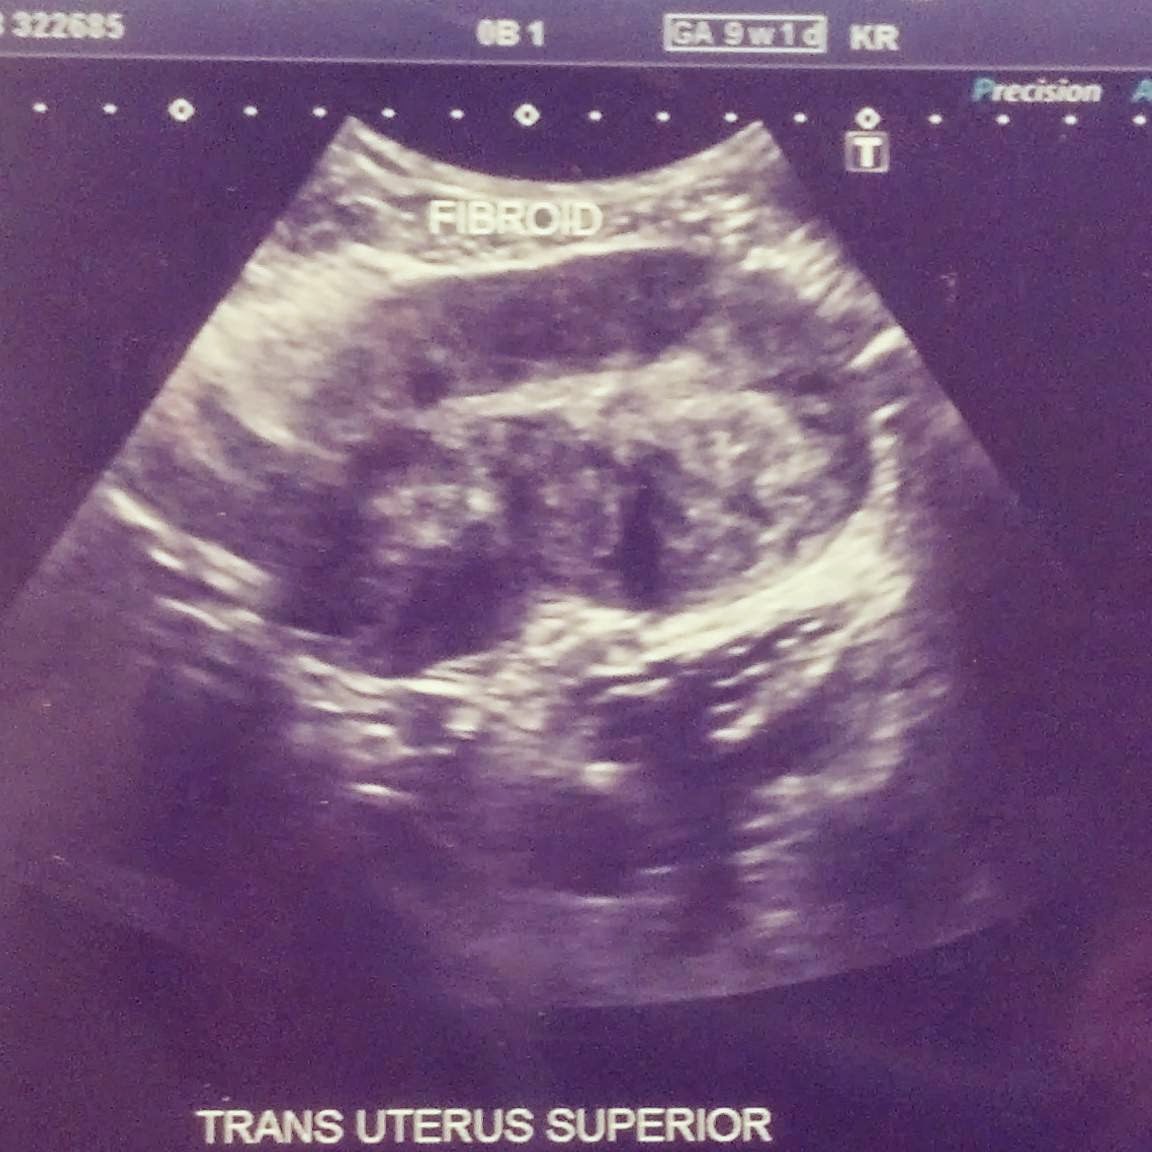

The ultrasound revealed the yolk sac but the technician couldn't detect the baby. She commented that it didn't mean for sure it wasn't in there, but that we just couldn't see it. (From what we understand now, we miscarried the day before when the bleeding first began.) What she could see though was something neither one of us were expecting...and they were, rather, alarming. Not one, not two, not three, but four fibroids...at least that she could see. She said there could be many more that she couldn't see as they tend to cluster together. Fibroids, what are those? Tumors she said. The largest was the size of a large potato, she said.

The ultrasound above is just one fibroid. This particular one is attached to the uterus via a stock, meaning that it is growing on the outside of the uterus. The three remaining are growing in the muscle lining of the uterus. Now let's back up. You ask me, "this one is how big? And you couldn't feel it? How could you have not known something this large was growing inside of you??" That is a great question. I did know something was growing inside of me and it was our baby. What I didn't know was the "bump" down there which was visibly protruding now, wasn't actually the baby, but indeed the largest of the four fibroids. What I learned later, was that due to my fibroids, my uterus was enlarged to a size 14 week pregnancy.